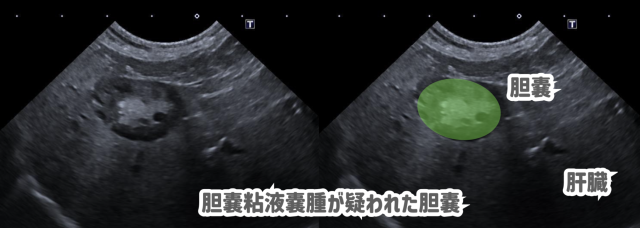

超音波検査では胆嚢内に不動性の貯留物が確認され、血液検査の結果と合わせて考え、胆嚢粘液嚢腫が強く疑われました。

胆嚢粘液嚢腫により胆嚢炎、肝炎が起こっていると考え、静脈点滴、抗生剤、制吐剤などによる入院治療を10日間行い、状態は良化していきました。

退院後も利胆剤を継続し、1ヶ月後の再診で血液検査は正常値に戻ったものの、胆嚢内の様子に変化が無かったため、胆嚢摘出手術と肝臓の細胞を一部採る生検を行いました。